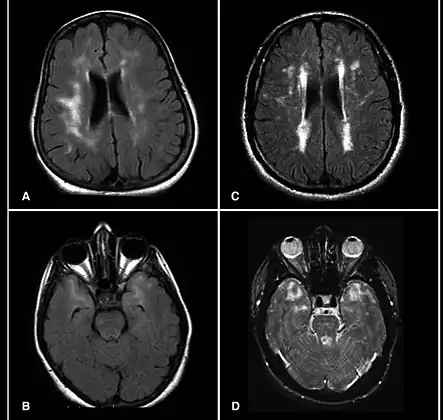

| Brain MRI from patients with CADASIL showing multiple lesions. | |

MRIs show hypointensities on T1-weighted images and hyperintensities on T2-weighted images, usually multiple confluent white matter lesions of various sizes, are characteristic. These lesions are concentrated around the basal ganglia, peri-ventricular white matter, and the pons, and are similar to those seen in Binswanger disease.[2][11] These white matter lesions are also seen in asymptomatic individuals with the mutated gene.[12] While MRI is not used to diagnose CADASIL, it can show the progression of white matter changes even decades before onset of symptoms.